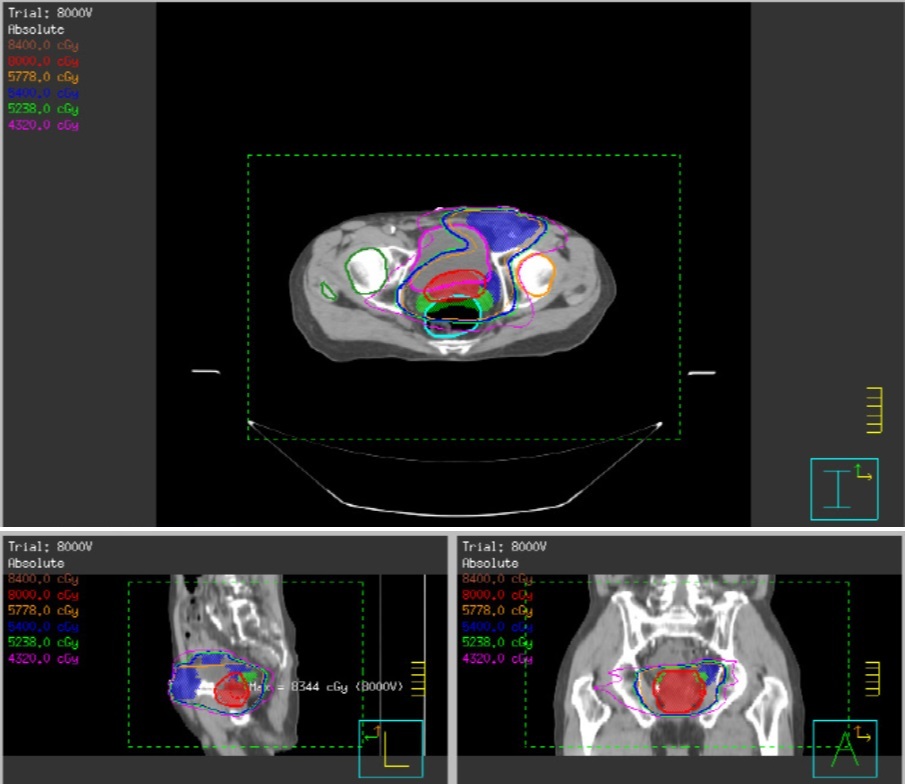

收治該病患的台北市立聯合醫院中興院區放射線腫瘤科醫師洪文欣表示,該患者年事已高,並且曾因冠心症放置過支架治療,麻醉風險極高,因此放棄手術治療,改以非侵入性的放射線治療,治療期間僅發生輕微腹瀉、裡急後重及照射患部皮膚發紅乾癢變黑等症狀,這些症狀在放療結束1至2週即逐漸消失。

洪文欣表示,攝護腺癌主要治療方式包含根除性手術、經尿道內視鏡電刀攝護腺刮除手術(TURP)、放射線治療、內分泌(荷爾蒙)治療(包含藥物或睪丸切除術)、冷凍療法、高能量聚焦式超音波(HIFU)或合併治療等。